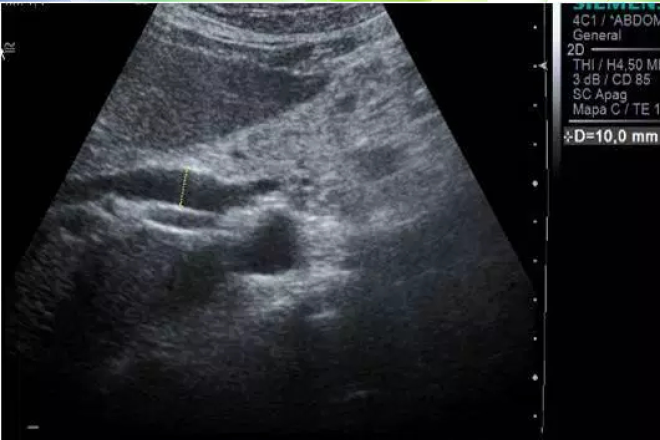

Sarcoidosis y carcinoma fibrolamelar del hígado

La sarcoidosis es una enfermedad de etiología desconocida que se caracteriza por la acumulación en los tejidos afectos de linfocitos CD4+ y monocitos, así como la presencia de granulomas no caseificantes que conducen a la alteración de la arquitectura tisular normal. En los lugares afectados la sarcoidosis se caracteriza por